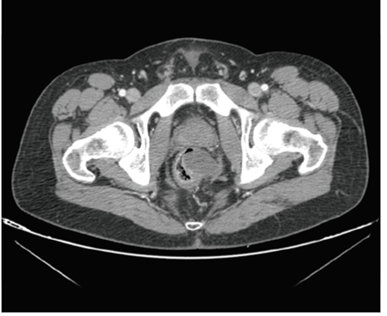

Finalmente, con los hallazgos clínicos, radiológicos y anatomopatológicos reunidos, se presentó en el Comité de Tumores Estromales, en el cual se decidió dar un tratamiento neoadyuvante con imatinib, con la intención de obtener una buena reacción y evitar una amputación abdominoperineal en este paciente. Se sometió a siete meses de neoadyuvancia acompañada de controles radiológicos periódicos. En el último control, se observó una disminución considerable del volumen tumoral, quedando este por encima de la reflexión peritoneal (figura 3). Se presentó nuevamente en el Comité con los hallazgos ac tualizados y se decidió indicar un tratamiento quirúrgico.